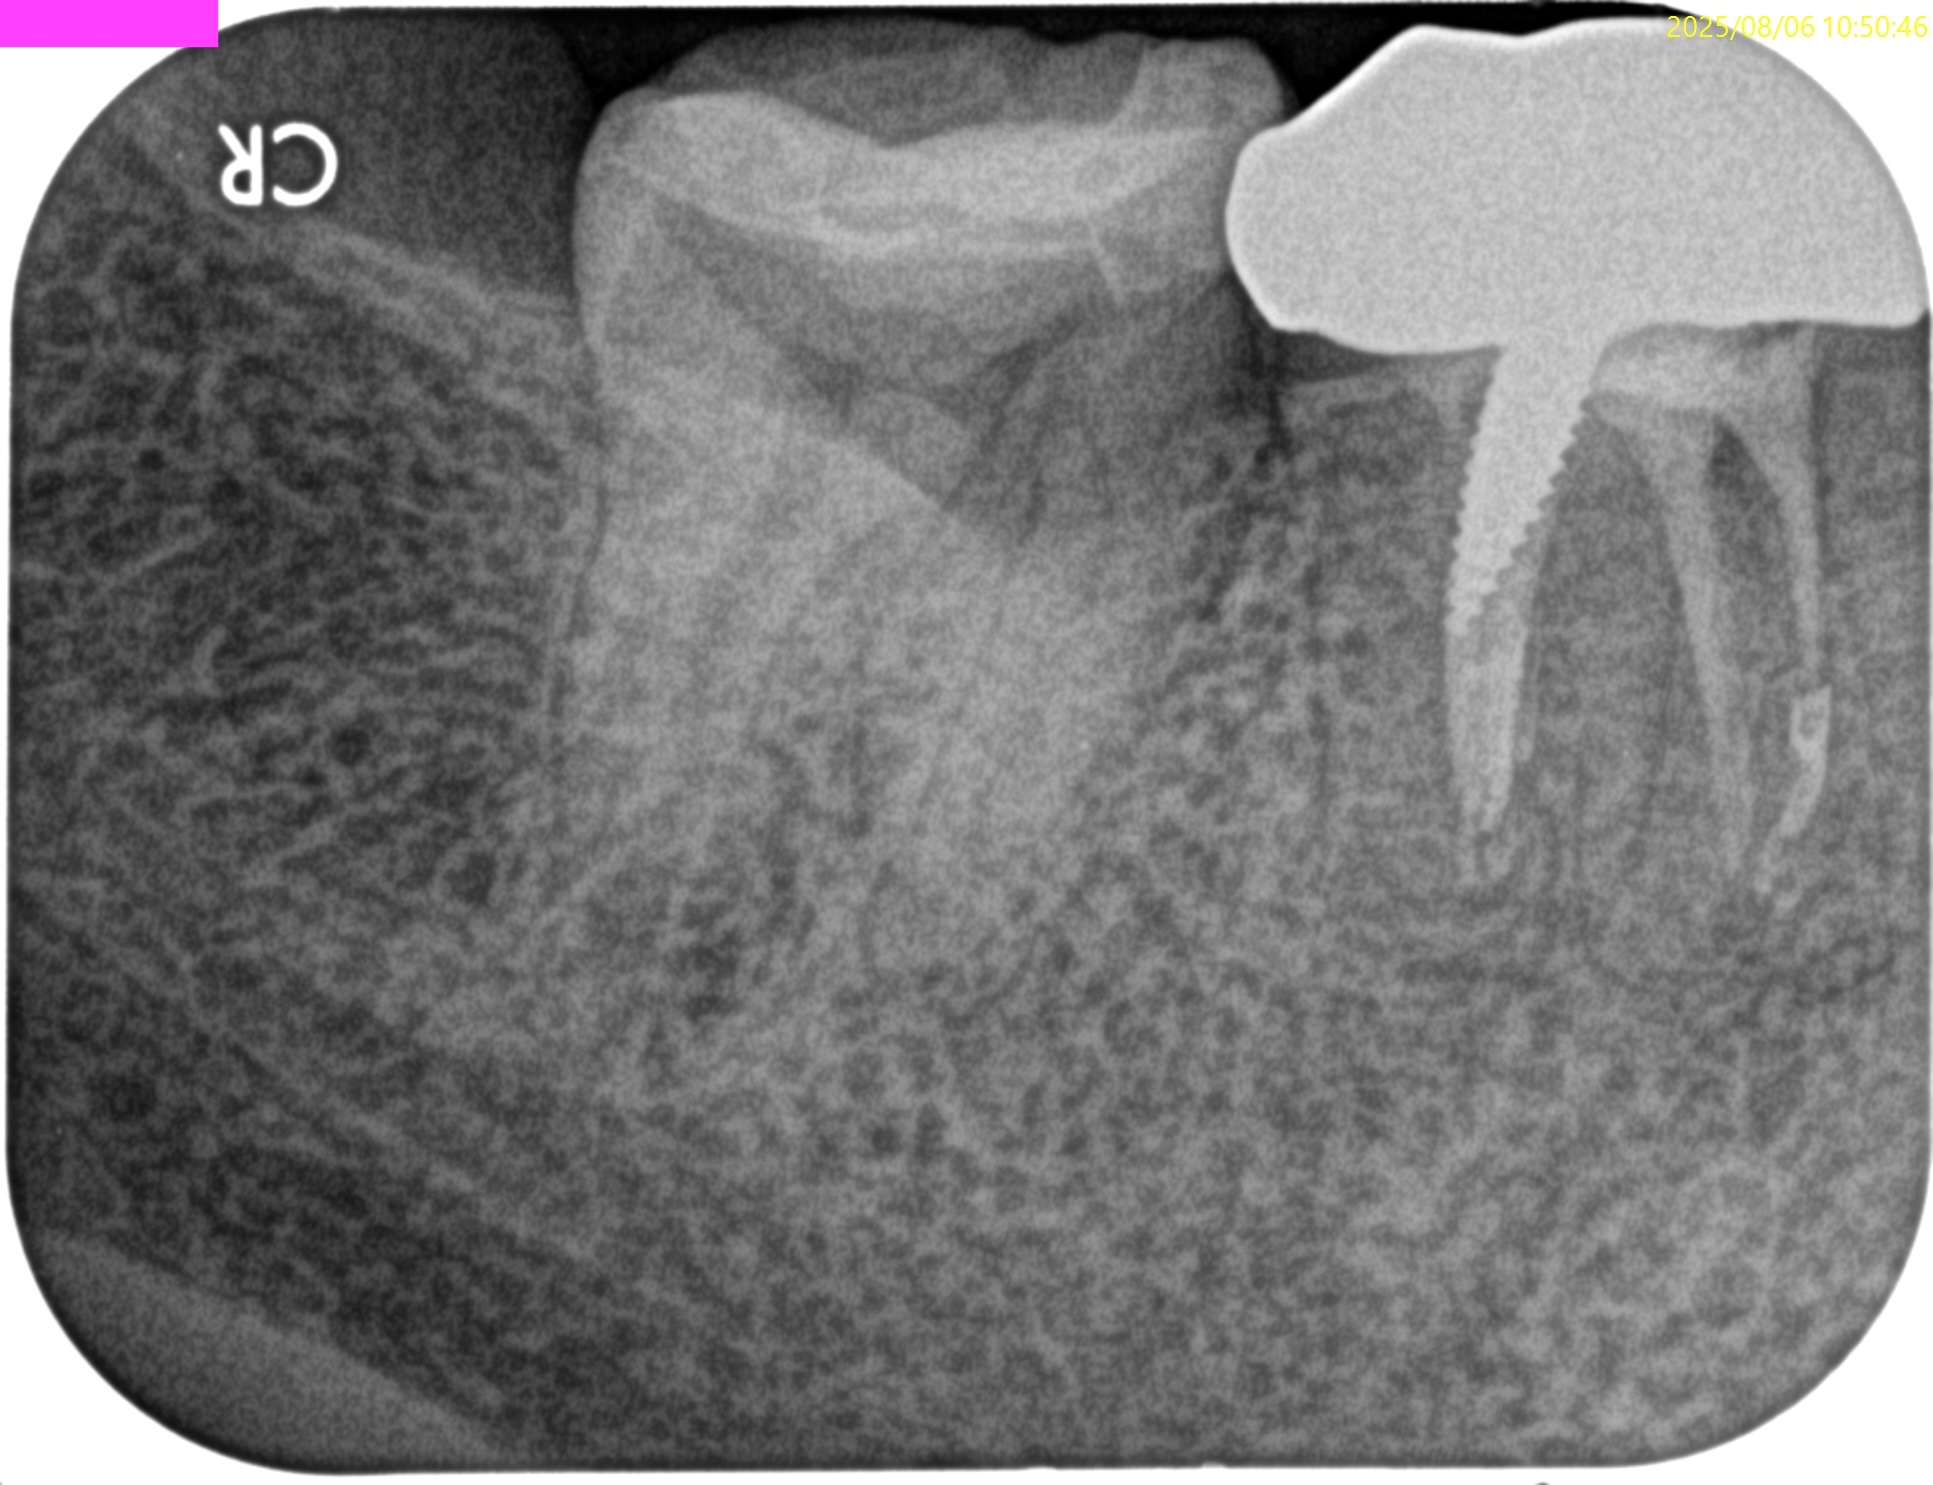

PA(2025.8.6)

#30には不完全な根管治療が、

#31には歯髄に近接する生活歯髄療法がなされている。

臨床症状から考えると、それぞれ根管治療が必要だろう。